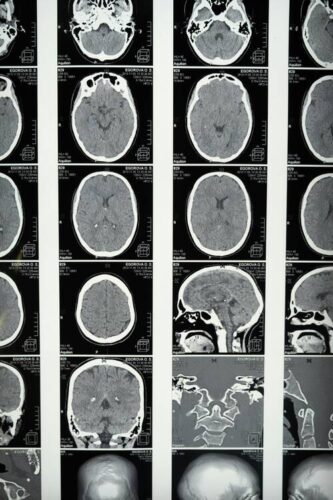

Additionally, AI-powered medical imaging tools analyze thousands of scans to detect abnormalities. Instead of radiologists manually reviewing every image, AI highlights areas of concern, significantly reducing diagnosis time. This structured approach enables medical professionals to focus on patient care rather than spending hours deciphering complex data.